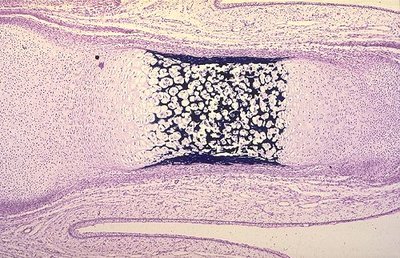

salut :) sa serait juste pour savoir si mon analyse sur cette photo qu'il a décrit ce matin était bonne , sur cette image mon périchondre est entrain de se transformer en périoste au centre de la diaphyse, y a l'apparition du cartilage hypertrophique mais pas encore d'invasion conjonctivo -vasculaire :) ??

Alors ici tu as bien ton début de périoste par contre je pense qu'il y a déjà un début d'ossification endochondrale (zone plus sombre) avec le périoste en périphérie :P